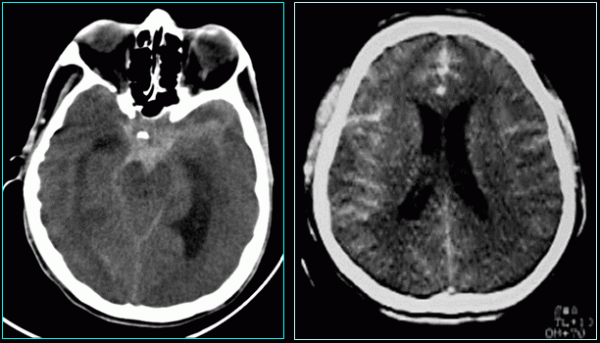

CHẨN ĐOÁN XUẤT HUYẾT NÃO

Bác sĩ có thể xác định một phần nào đó của não bị ảnh hưởng dựa trên các triệu chứng người bệnh gặp phải. Bác sĩ có thể đề nghị người bệnh thực hiện các xét nghiệm hình ảnh, chẳng hạn như chụp CT để phát hiện xuất huyết nội hoặc máu tụ. Phương pháp khám thần kinh hoặc khám mặt cũng có thể giúp phát hiện được phù dây thần kinh thị giác. Chọc dò tủy sống thường không được thực hiện, vì phương pháp này có thể gây nguy hiểm và khiến bệnh xấu hơn.